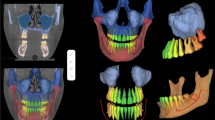

AI enhances early diagnosis through diagnostic algorithms that guide investigations based on clinical and radiological data. AI-driven image analysis enables accurate segmentation of intricate structures and extraction of radiomics data, optimizing preoperative planning and predicting treatment response. In surgical planning, AI aids in identifying critical structures, leading to precise interventions. Real-time AI-based navigation offers adaptive guidance, enhancing surgical accuracy and safety. Predictive analytics empower risk assessment, treatment planning, and outcome prediction. AI-driven clinical decision support systems optimize resource allocation and support shared decision-making. Postoperative care benefits from AI’s monitoring capabilities and personalized rehabilitation protocols. Virtual simulations powered by AI expedite skill development and decision-making in complex procedures.